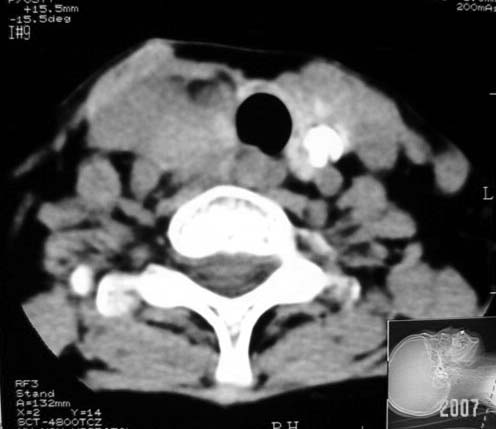

标题: CT7324:女57岁,右颈部肿物2年.

右甲状腺内占位密度均匀边缘规整考虑腺瘤可能性大

右侧甲状腺区均匀密度软组织肿块,无坏死及钙化,边缘光整,与周围组织分界清晰,病史较长,首先考虑右侧甲状腺腺瘤。